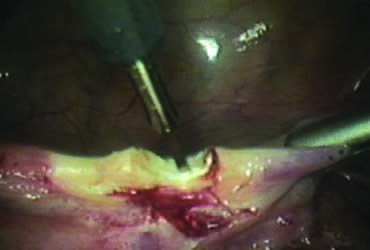

The right round ligament is held in its midportion, coagulated with bipolar forceps, and cut (Fig. 1). The anterior leaf of the right broad ligament is incised parallel to the uterus, and the incision is curved medially over the cervix (Fig. 2). The same two steps are repeated on the left side, and the incisions are connected (Fig. 3). The bladder flap is mobilized out of the surgical field by cutting the cervicovaginal septum, as needed. Coagulation and cutting the superficial upper portions of the lateral vesicouterine ligaments or bladder pillars completes the dissection.

Fig. 1. Coagulation and cutting of round ligament.

Fig. 2. Incision of the anterior leaf of the broad ligament.